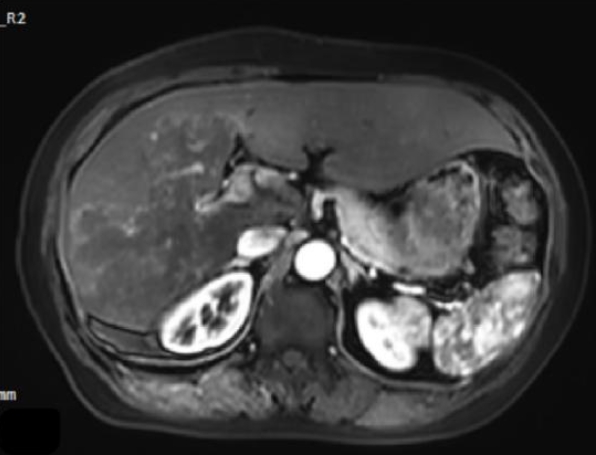

Ultrasound showed a heterogeneous hyperechoic mass (7.8×5.5 cm) with unclear borders in liver segments S4, S7, and S8 (Fig. 1). Computed tomography suggested a large, poorly defined mass with mixed density and patchy calcifications (maximum cross-sectional area 15.11×11.29 cm) in the liver. No enhancement was observed in dynamic contrast imaging. A low-density lesion in the left adrenal gland showed no enhancement (Fig. 2A). The right portal vein was narrowed. The right and middle hepatic veins were partially obscured in the portal venous phase (Fig. 2B). The presence of a large, infiltrative mass with heterogeneous density and irregular calcifications is a recognized, though not universal, imaging presentation of advanced alveolar echinococcosis, which can mimic malignancy.

Fig. 1.

Abdominal color doppler ultrasound showed a heterogeneous.

Fig. 1. Abdominal color doppler ultrasound showed a heterogeneous.